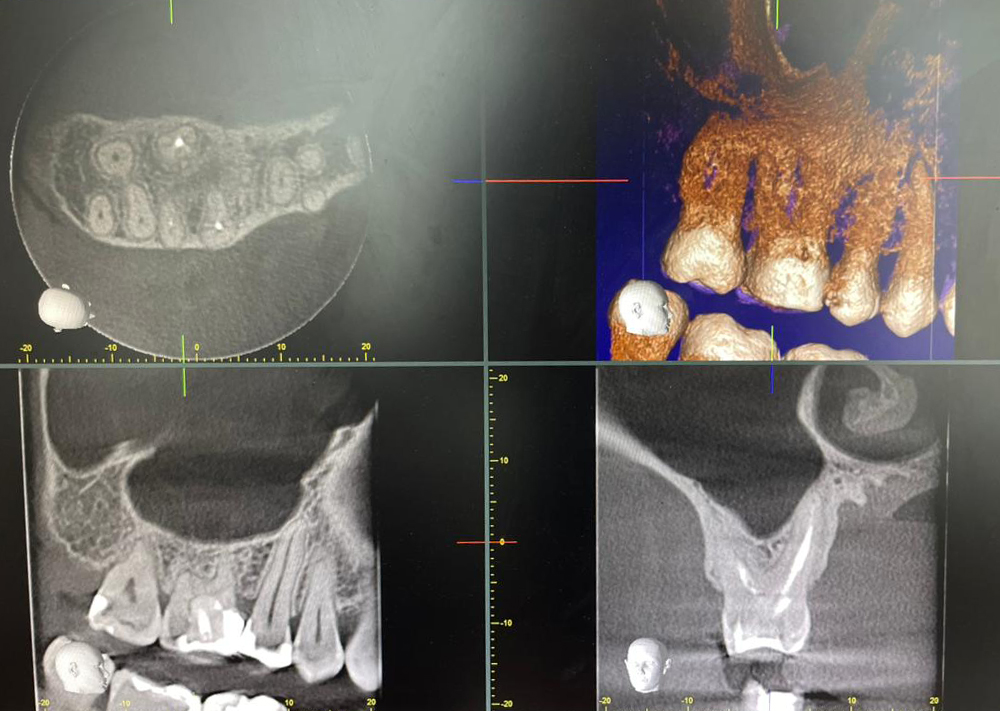

Сучасна рентгенологічна система Veraviewepocs 3D від компанії Morita поєднує три види знімків в одному апараті: панорамний, цефалометричний та 3D КТ (конусно-променеву томографію). Це дозволяє лікарю отримати максимально точне зображення зубів, щелеп та навколишніх структур для детальної діагностики і планування лікування.

• Точне 3D-зображення усіх анатомічних структур, включно з коренями зубів, каналами, кістковою тканиною та верхньощелепними пазухами.

Veraviewepocs 3D використовується для імплантології, ендодонтичного лікування, ортодонтії, хірургії та складних діагностичних випадків. Це надійний інструмент, який допомагає лікарю бачити найдрібніші деталі і приймати точні клінічні рішення.